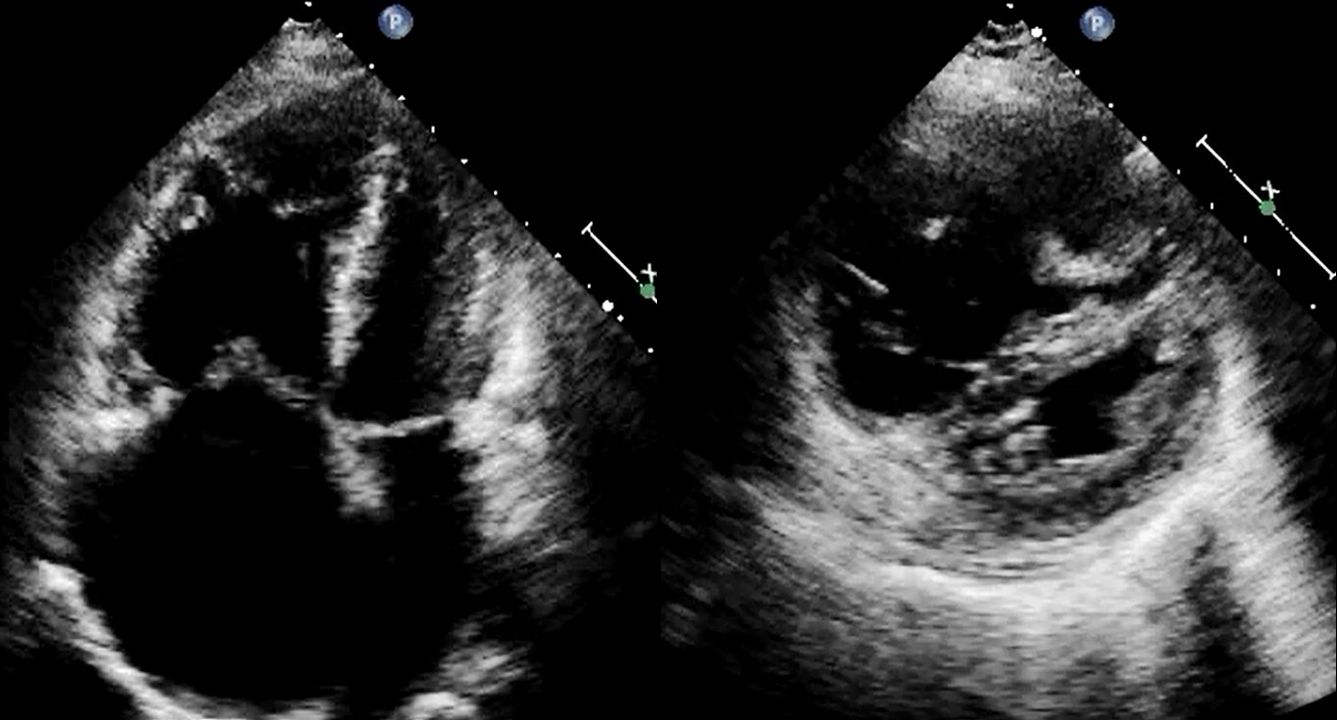

慢性血栓塞栓性肺高血圧症